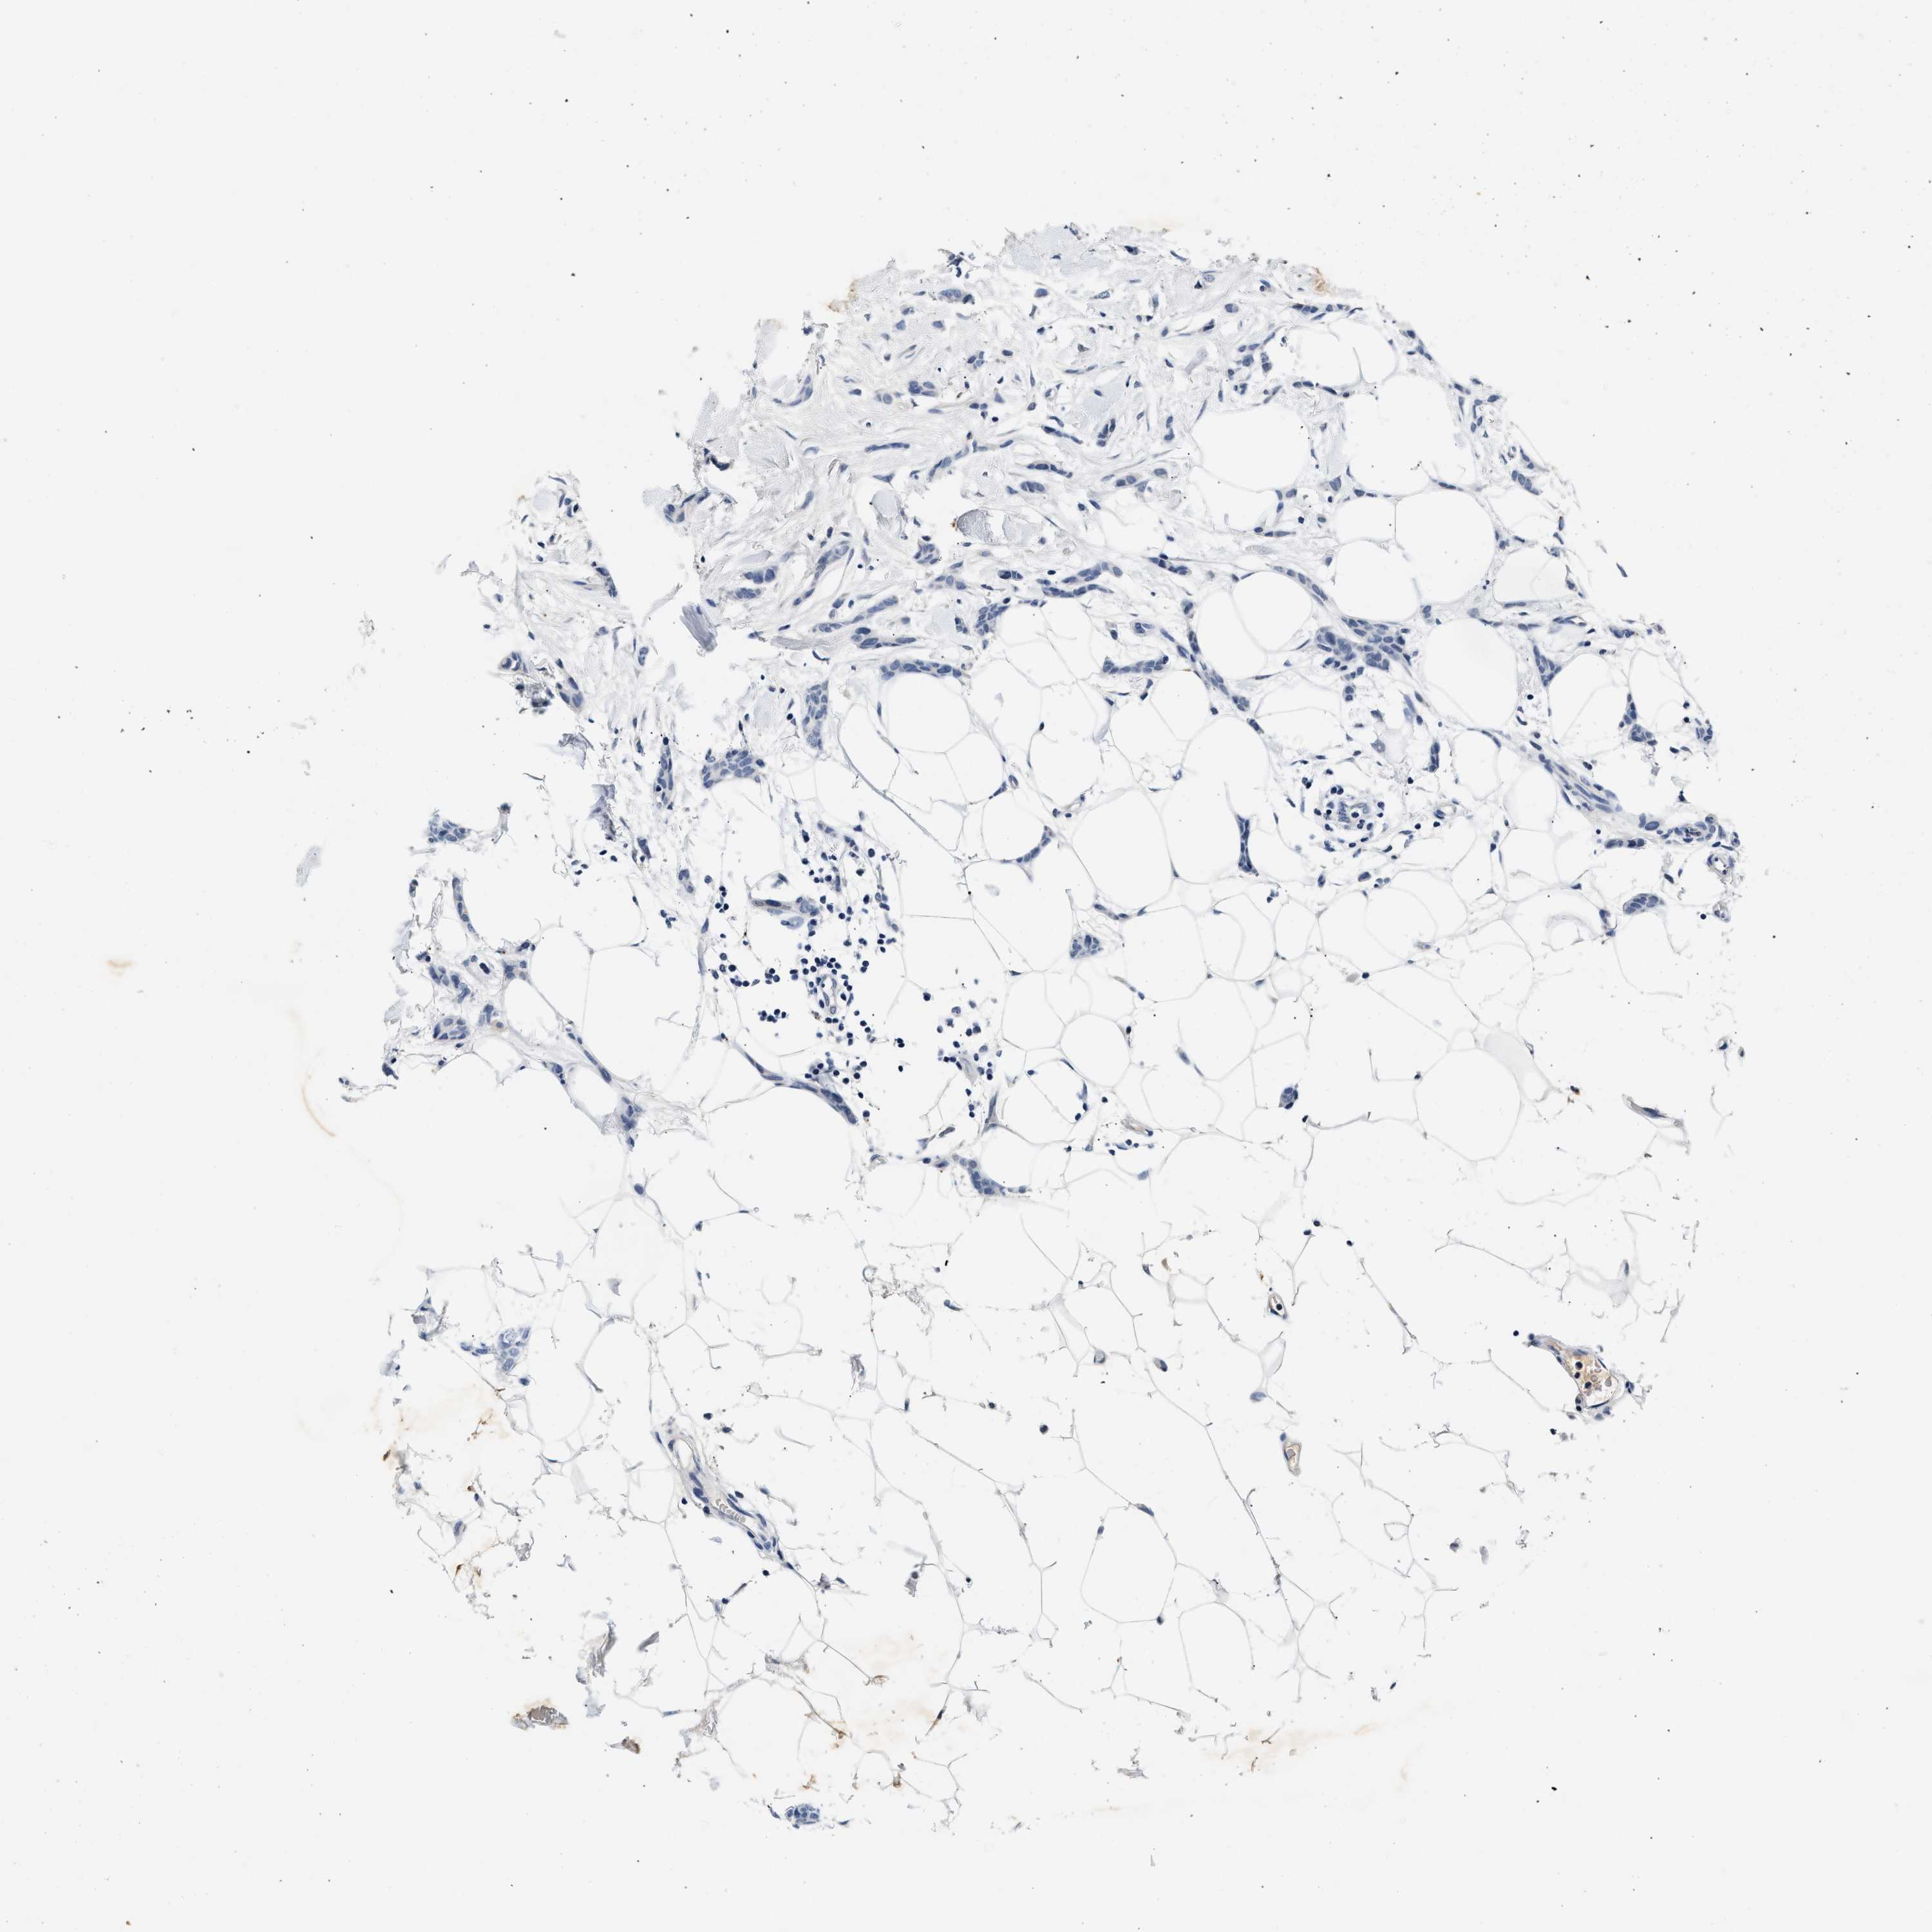

CANCER BREAST CANCER Show tissue menu

BRCA TCGA BRCA VALIDATION PROTEIN EXPRESSION